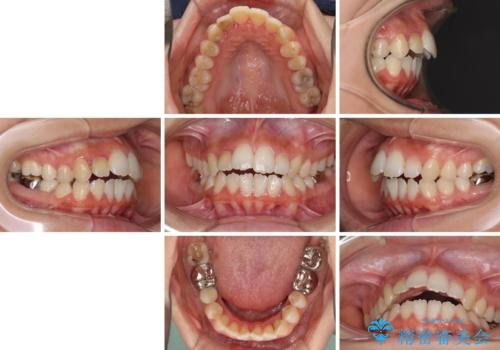

開咬と前突を改善 ワイヤー装置での抜歯矯正

- 口元の突出感と開咬を気にして来院された患者様です。

口元の突出感を改善するため、第一小臼歯を抜歯して口元を引っ込めることとしました。

一般的には上下左右の第一小臼歯4本を抜歯しますが、下顎に対して上顎が前方に位置しているため、まずは上顎小臼歯2本を抜歯し、治療経過を見て下顎小臼歯を抜歯するかどうかを決めていくこととしました。

元々むし歯の処置歯が多く、神経を取り除いている歯が多くありましたが、どうやら右上の前歯と小臼歯は外傷により神経を失った可能性があり、抜歯したスペース前後の歯が全く動かない状態でした。

結果として下顎の小臼歯は抜歯せず、右上の抜歯スペースはむし歯処置を兼ねてオールセラミックブリッジにて補綴治療を行うこととしました。

動かない歯での停滞や、出産と子育てなどにより治療期間は長期化しましたが、整った歯列にて仕上げることができました。